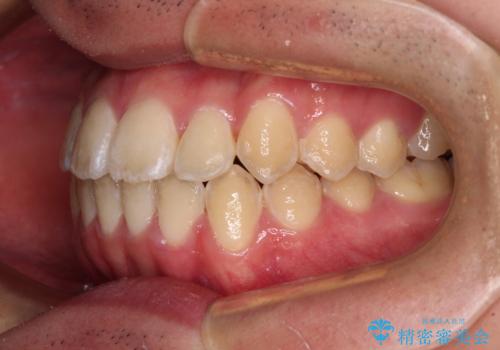

- 上下前歯のデコボコを気にして来院された患者様です。

ワイヤー矯正でもマウスピース矯正でも可能でしたが、短期間で、自身の手を煩わせることなく治療を行いたいとのことで、ワイヤー装置にて矯正治療を行うこととしました。

当初予定通り、1年間で治療を終えることができました。